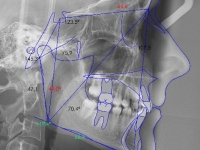

Clase II paciente 15 años

Ago

2013

2013

26

La paciente O.O. acude a nuestra consulta por:

– Canino 13 e incisivo lateral 42 en posición ectópica.

– Canino 23 incluido.

Con lo que decide realizarse un tratamiento de ortodoncia de duración de 24 meses con brackets damon Q.

CASO COMPLETO: